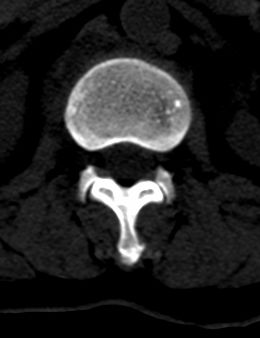

患者 女 54岁 外伤后检查发现l1椎体局部密度减低,请问这是什么病灶?

椎体内部局限性骨小梁稀疏、粗大改变,周围未见软组织肿块,首先考虑椎体血管瘤。